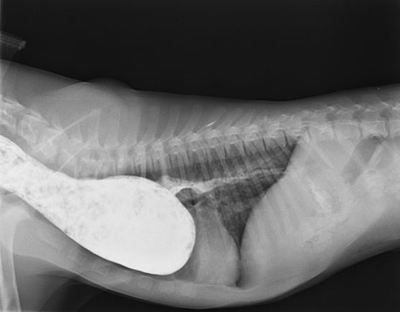

PRAA - Dog

At Veterinary Specialist Services, we work closely with a number of charities including the Royal Society for the Prevention of Cruelty to Animals (RSPCA). This week, it was all heads together, as we collaborated on a very complex case. The goal to fix a 6 month old puppy with a history of regurgitation (bringing up food). The condition was severe enough that he was unable to hold food down at all. The puppy was extremely underweight because of this. Imaging revealed that he had a stricture of the oesophagus at the heart base (within the chest) so food was not passing normally into his stomach. With further imaging and gastroscopy, we were able to diagnose a Persistent Right Aortic Arch. This is a congenital abnormality located in the chest, where one of the embryonic arches that forms the heart, persists and forms a ring that traps the oesophagus. This condition requires advanced surgery. The only way to remove this ring around the oesophagus is to explore the chest surgically and ligate the ligament that is causing the problems.

This involved a huge team effort between Veterinary Specialst Services, Animal Emergency Services and the RSPCA. Our cardiologist Dr Fiona Meyers helped to diagnose the condition, our surgeons Adjunct Professor Philip Moses and Dr Abbie Tipler performed a thoracotomy (opening the chest) to ligate the ligament in front of the heart, our highly trained nurses monitored the anaesthesia, the emergency service AES cared for the patient intensively overnight and the wonderful team at the RSPCA picked the patient up the next day to take him to a loving foster carer who will care for him until he is recovered enough to go to his new home. A big thanks to all the hard work by everyone and we were very pleased with the outcome for this little puppy. This radiograph is a barium study showing barium collecting in the dilated constricted oesphagus in front of the obstruction.